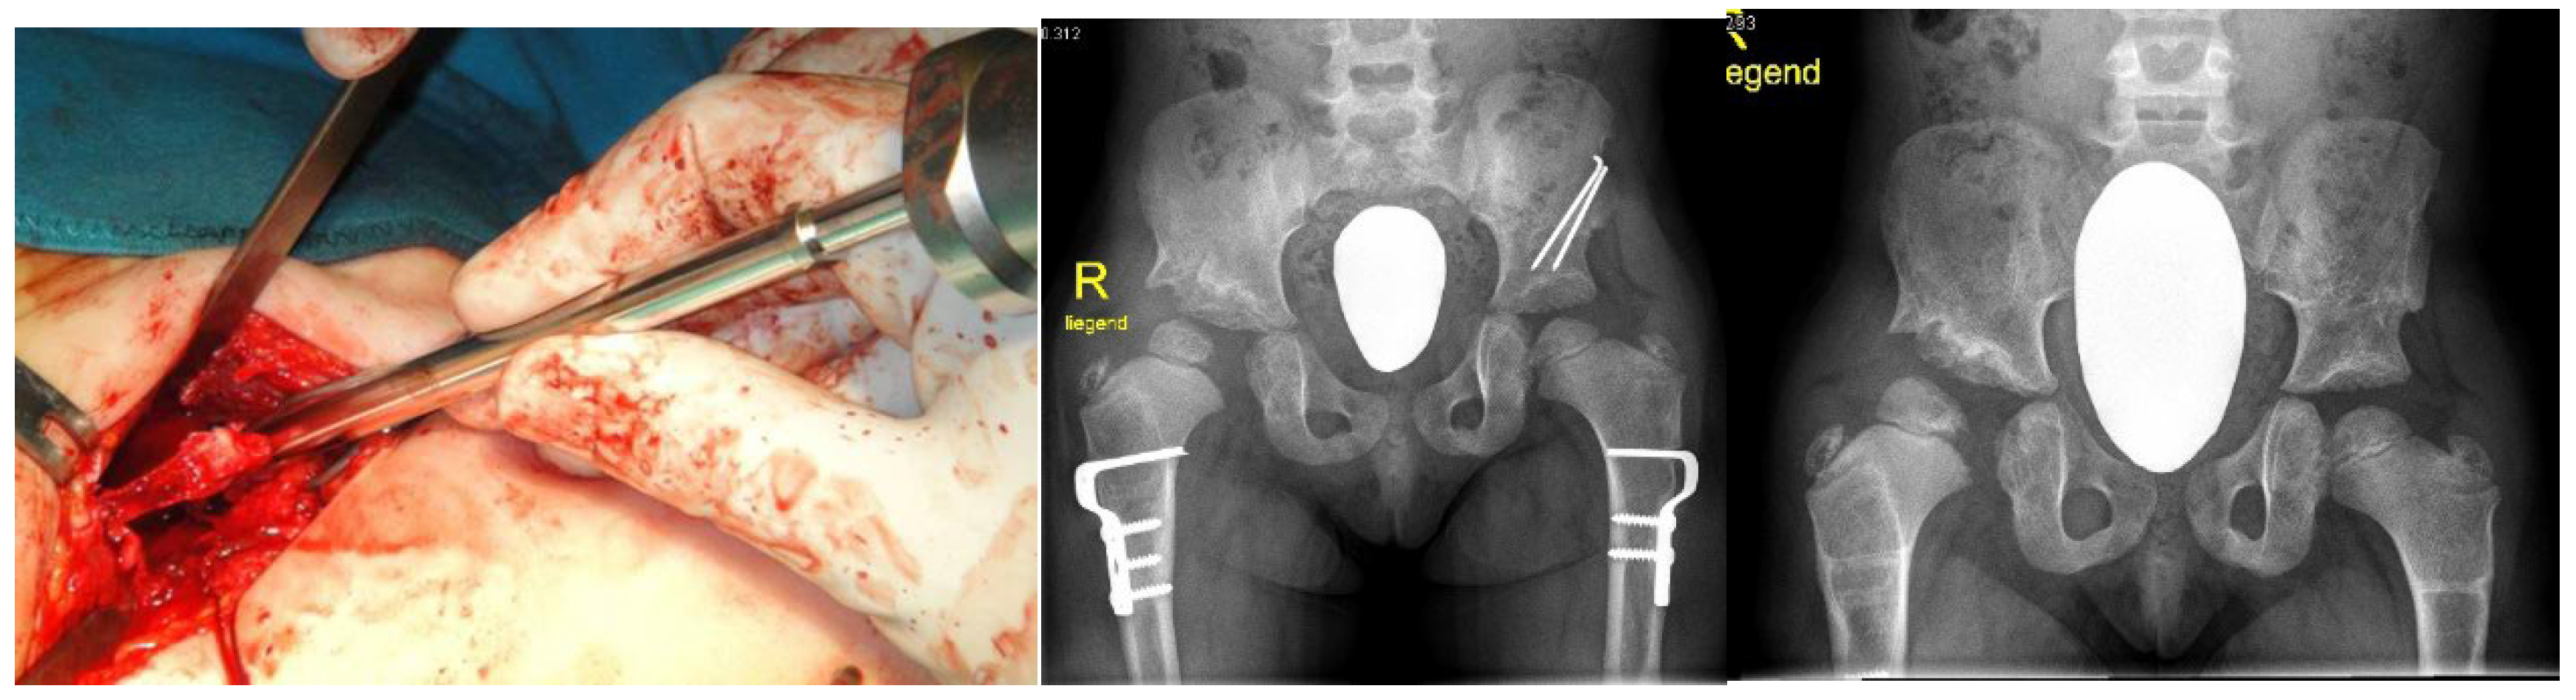

3.4. Surgical Interventions to Correct Hip/Knee Dislocations and Talipes Equinovarus

3.5. Surgical Intervention to Correct Traumatic Tertaplagia